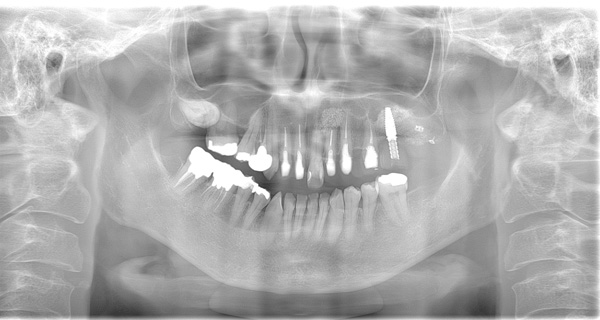

AFTER

| 年代・性別 | 50代 女性 |

|---|---|

| 主訴 | 左上のブリッジがグラグラして外れそう |

| 治療期間 | 約18ヶ月 |

| 費用 | 1,600,000円 |

| 治療内容 | インプラント、骨造成、サイナスリフト、セラミック修復 |

| 治療に伴うリスク | インプラント周囲炎 セラミックの破折、脱離 |